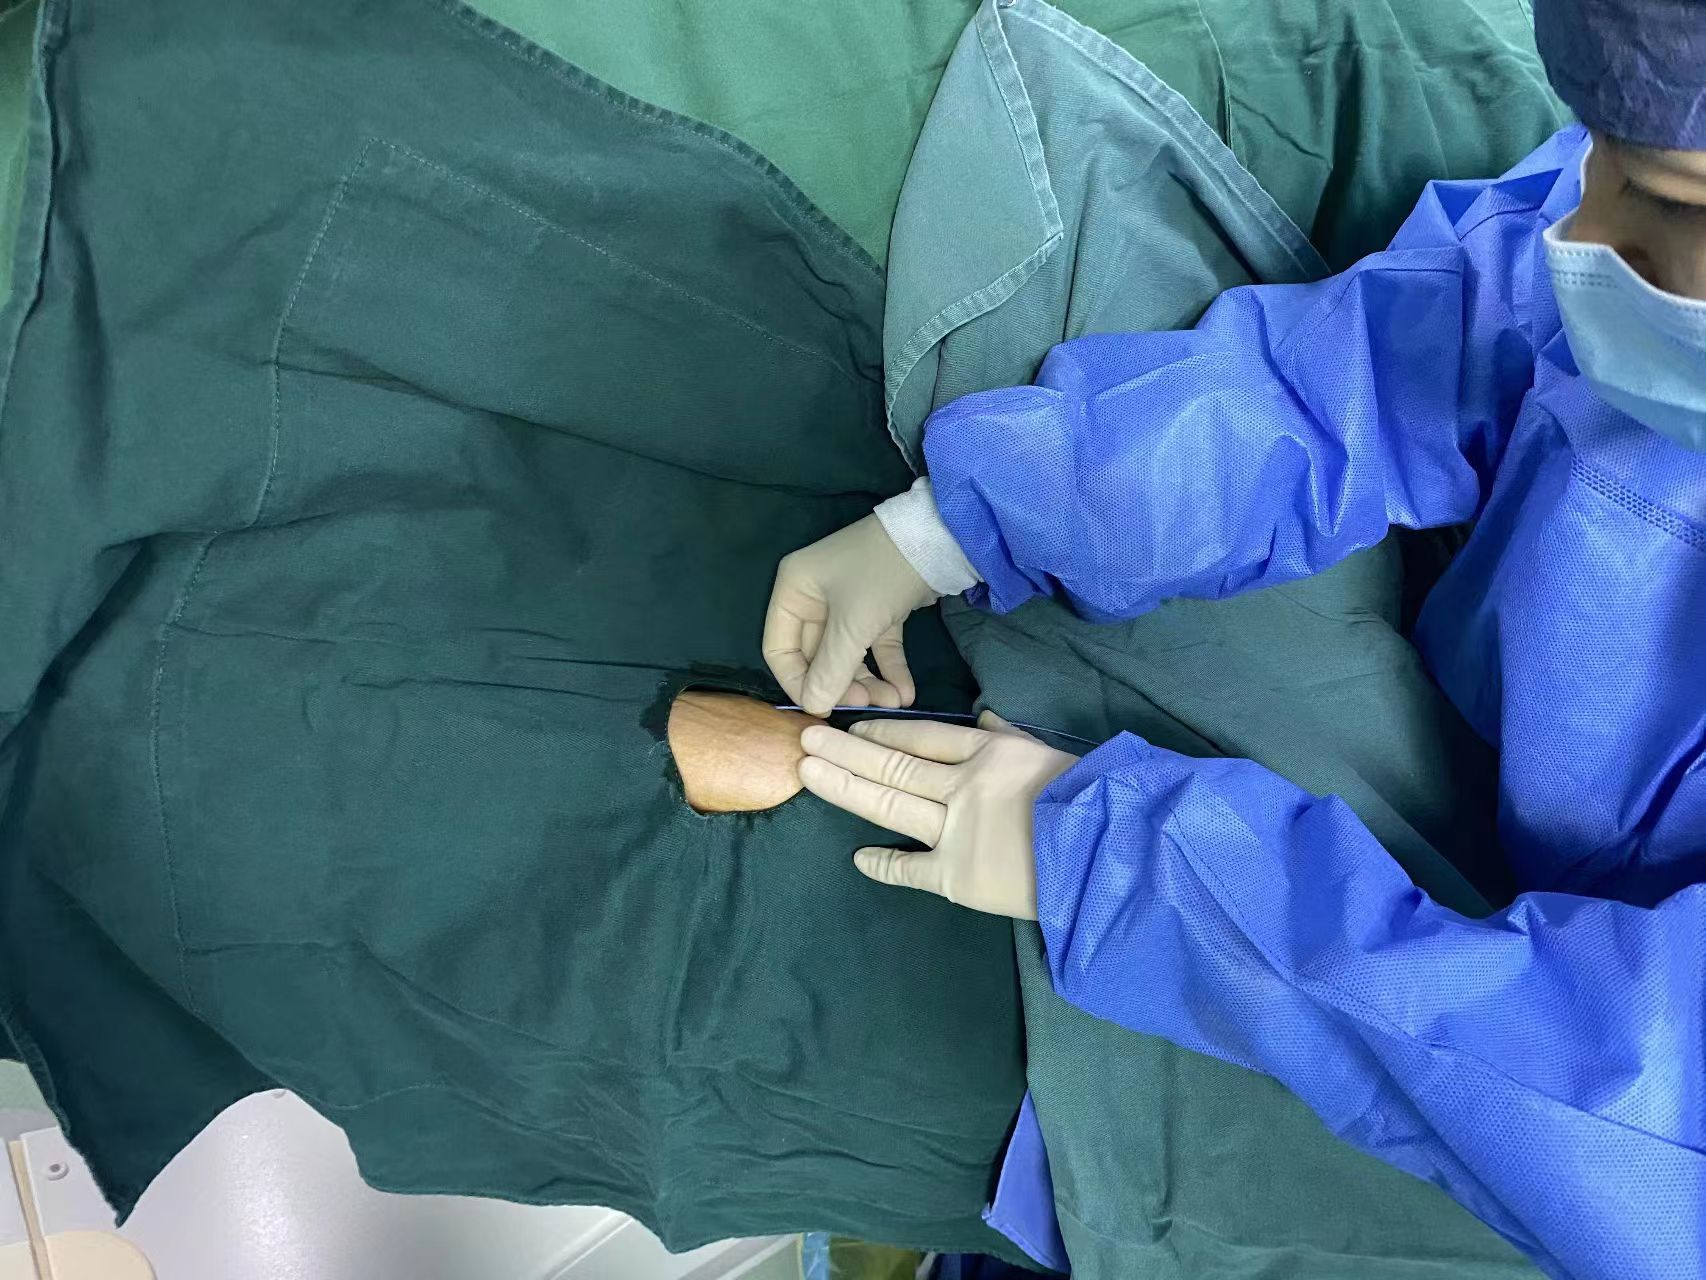

“高大伯,您放心,导管已经调整好,后期您做好维护,可以使用一年,以后再也不用怕打针了”。静疗专项小组组长冯尼尼亲切地和高大伯说明情况,高大伯会心地笑了。

正当我们为此一筹莫展之际,放射科冯国灿主任建议我们可以利用数字减影血管造影技术(DSA)进行调整置管,这个建议让我们看到了希望。我们本着以“患者为中心,患者利益至上”的原则,通过对DSA技术的原理和仪器的操作进行全面学习,并在放射科的配合下和心内科郭张财主任的指导下,成功置管,保障患者治疗方案正常开展。